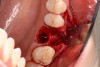

2. The remaining socket should be cleaned and curetted of all remaining granulation tissue or residual soft tissue present at the apex, especially with endodontically treated teeth (Figure 5).

Fig 5. Clean any granulation tissue out of the socket to create a clean wound free of debris.

Figure 5